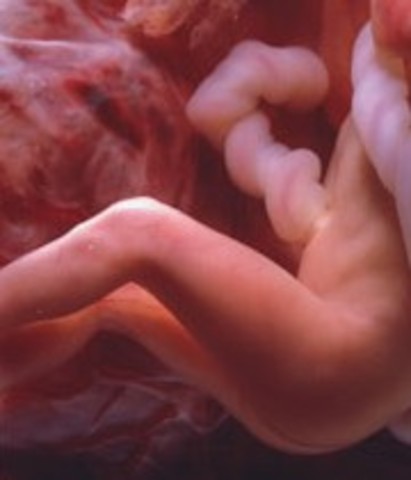

• Week 7: Arms and Legs

Week 7: Arms and Legs

Now at 13 mm in length, the embryo's organs are beginning to take its shape. Vocal cords, mouth, digestive tract, etc are beginning to form. Somewhat eyes are appearing, legs and arms are developing.

Facts: -The heart is beating with one chamber

-A dividing wall is formed in the heart